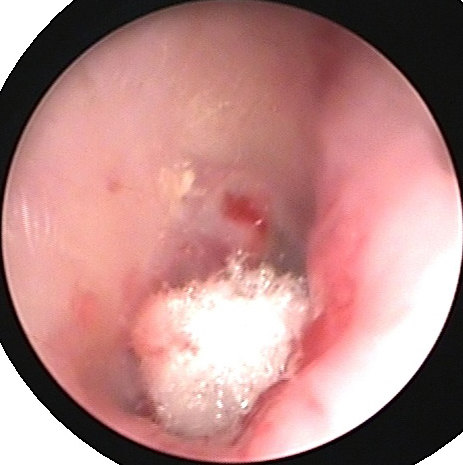

患者1 鼓膜后部穿孔,接受微创耳内镜下手术治疗,术后2周可见鼓膜已经